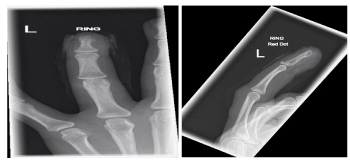

A 38 year old right handed lady presented to the emergency room with the beater component of an electric hand whisk entangled through the pulp and nail complex of the left ring finger, with ischaemia of the fingertip (Figures 1-3). The injury was sustained as the removable metal beater was replaced into the machine, while the electrical hand whisk was powered on, resulting in the beater rotating immediately and thereby intertwining the ring finger in the spinning metal. Plain radiographs were performed to evaluate for fractures and assess the position of the metal loops of the whisk (Figures 4-5). Due to the extent of the twisted metal around the finger, there was initially uncertainty as to whether Emergency Department staff ought to remove the whisk.

Figures 4-5. Anteroposterior and lateral radiographs of the ring finger with the metal whisk in situ